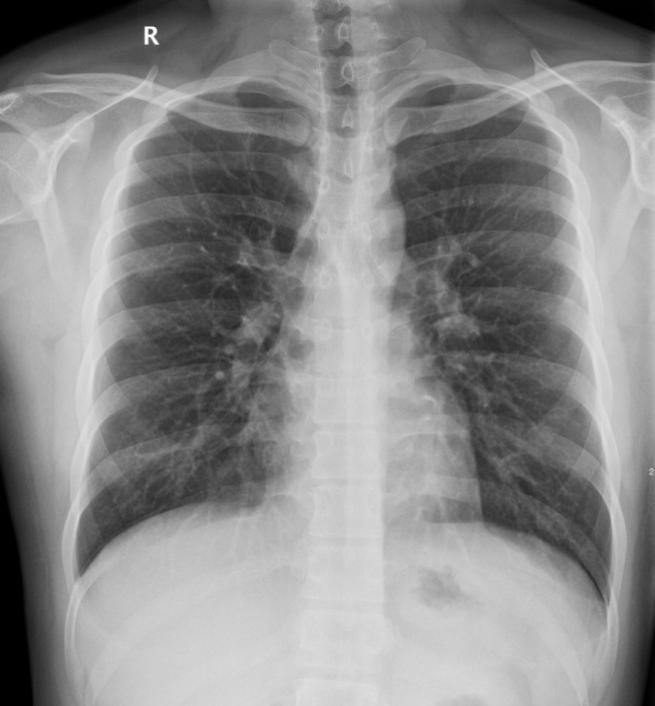

1. X线摄影:也就是我们日常所说的拍片,是最基础的放射检查方法。它操作简便、检查速度快、费用相对较低,常用于检查骨骼系统疾病,如骨折、骨肿瘤等。当我们不小心摔倒怀疑骨折时,拍一张X线片,就能清楚地看到骨头是否断裂以及断裂的位置和程度。在胸部检查方面,X线胸片可以帮助医生发现肺部的一些明显病变,如肺炎、肺结核、肺部肿瘤等,但对于一些早期或较小的病变,可能容易漏诊。

正常胸片和左锁骨骨折